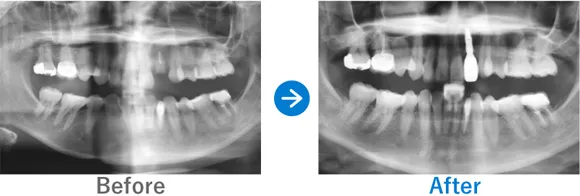

Case1

奥歯をインプラントに。ガイド&10年保証ありでコストパフォーマンス◎

左下6が破折して抜歯

インプラント1本:左下6

308,000円(内訳:インプラント1本(ネオデント)、ガイド、仮歯、保証10年)

来院の背景

右下の奥歯が破折したため、抜歯。インプラントを検討し来院されました。できるだけ見た目よく仕上げてほしいとのご要望もありました。

治療結果

骨の治癒がよく骨幅もあったため、骨造成をすることなくインプラント手術ができました。噛む力が強いため、今後は噛み締めや食いしばりによるインプラントへの負担を軽減していくことがポイントです。対策方法としては、マウスピースやボツリヌストキシン注射などがあります。また、定期的なメンテナンスも重要です。